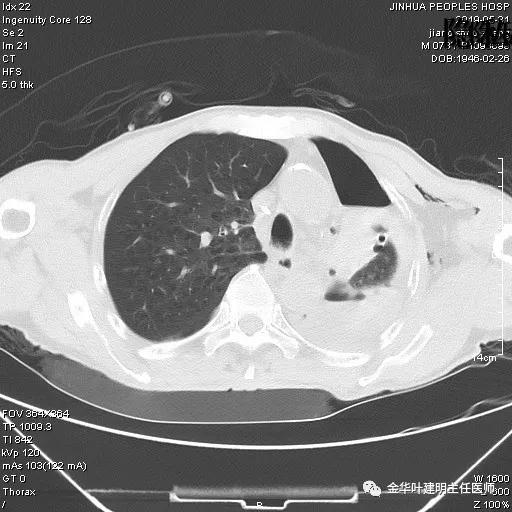

6.4上午:24小时引流出血性乳糜液1800毫升。是否再次手术进行右进胸胸导管结扎,抑或继续保守治疗非常纠结!压力非常大!!多方讨论会诊无法取得一致意见,但一般认为,引流量在1000毫升以上宜积极手术。情况与浙二医院范军强教授联系,请求指导,范教授认为左侧肺手术,损伤胸导管主干的机会较小,多数可保守治疗而愈。在他们的病例中,也有结扎胸导管后引流量仍无减少,效果并不能完全保证。建议可以考虑胸管夹管观察(因为淋巴管压力低,予以适当的压力,漏出量可能会明显减少),同时继续禁食,并静脉营养支持,引流管口可能会有渗液,注意更换敷料。与家属充分沟通后决定试夹管;这天血色素9.0 g/L;胸部CT复查示: